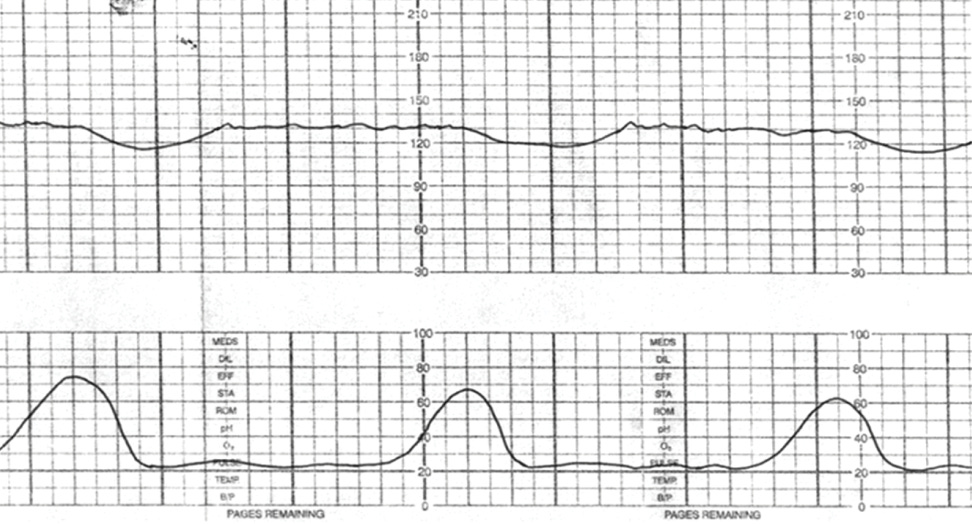

Cardiotocography, known simply as “fetal monitoring” in American labor wards, arrived in the 1960s with an elegant premise. Two sensors. Two tracings. One captured the fetal heart rate as an indicator of fetal wellbeing; the other recorded uterine contractions as the physiologic stressor…